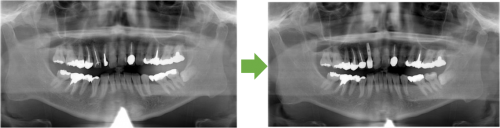

術 前 術 後

川口の歯科 歯医者 さかえ歯科クリニック

2014年12月16日